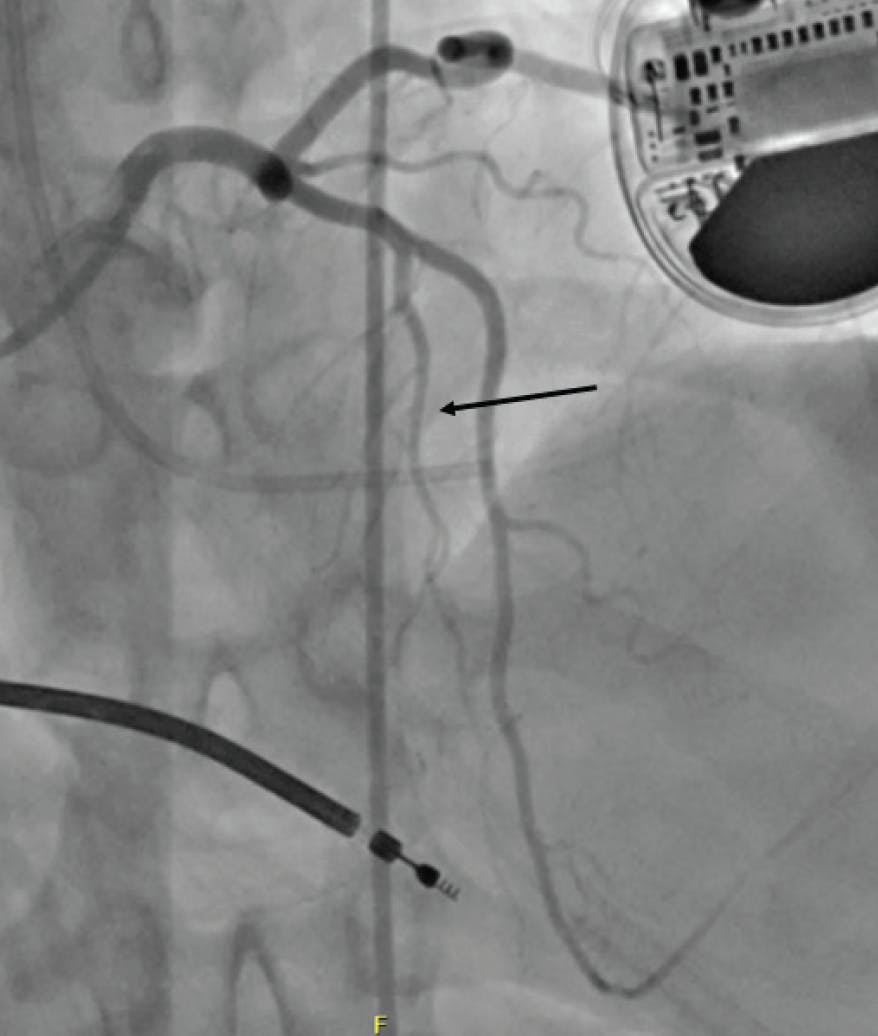

A careful review of the echocardiogram should confirm significant obstruction (> 50 mm Hg at rest or with provocation), systolic anterior motion (SAM) of the mitral valve, and “adequate” septal thickening (usually ≥ 1.5 mm). Most importantly, the septal anatomy requires careful review. The ideal anatomy is a proximal first septal perforator from the left anterior descending artery (LAD) that is about 1.5 mm in diameter and reaches not much farther than the midseptum (Figure 1). However, septal anatomy varies greatly, and some varieties are not suitable for ASA. For example, there may be an array of very small septals, or the proximal septals may be too small to instrument or unlikely to supply the correct place in the septum to eliminate obstruction (Figure 2). Alternatively, there may be a single, very large septal perforator that supplies a large amount of nontargeted myocardium (Figure 3). Note that septal perforators may arise from vessels other than the LAD, including the proximal diagonal, ramus, left main, and even right coronary arteries. The operator should review the baseline electrocardiogram. Because a right bundle branch block occurs in 40% of patients undergoing ASA, a pre-existing left bundle branch block is associated with a very high risk for permanent pacemaker.

Figure 2. In this patient, the first septal perforator (single arrow) is a very small vessel, and injection with alcohol is unlikely to impact the gradient. A larger second septal perforator (double arrow) supplies the midseptum distal to the SAM contact point, and injection in this vessel will not impact the gradient.